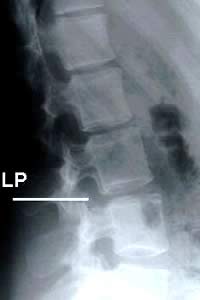

⭕ لاحظ... من يأخذ العينه يجب أن يكون دكتور⬅️ لأنه يعرف كيف يتصرف عند حدوث أي مشكله أثناء السحب وكذلك ملم بتشريح الجسم و لصعوبة اخذ العينه.

?يجب أخذ الإحتياطات اللازمه قبل جمع العينه لأن أي خلل سيقود إلى مضاعفات كثيره..

? جمع العينه يكون في بيئه معقمه وبحذر شـــديــــد

? المرضى اللذين يعانون من سيولة الدم او تخثر الدم ممكن أن يسبب لهم أخذ العينه نزيف في الحبل الشوكي..